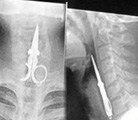

恐怖!X光下的體內異物